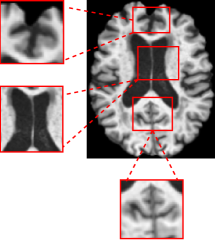

where Conv3Dk\mathrm{Conv3D}_{k} denotes a 3D convolution with kernel size kk, and x(l)x^{(l)} is the resulting feature map. To preserve anatomical boundaries, and restrict the transformation to foreground regions, a binary foreground mask M=𝟙x0{0,1}B×1×D×H×WM=\mathbbm{1}_{x\neq 0}\in\{0,1\}^{B\times 1\times D\times H\times W} is applied at each layer. As shown in (Fig. 3), the dilation-based transformation produces outputs that mimic the expanded appearance typical of healthy brain anatomy in NC cases.

Refer to caption

(a)

(b)

Figure 3: Visualization of a pseudo-dilation result. (a) Original NC image from the dataset. (b) Resulting image after applying the pseudo-dilation module.